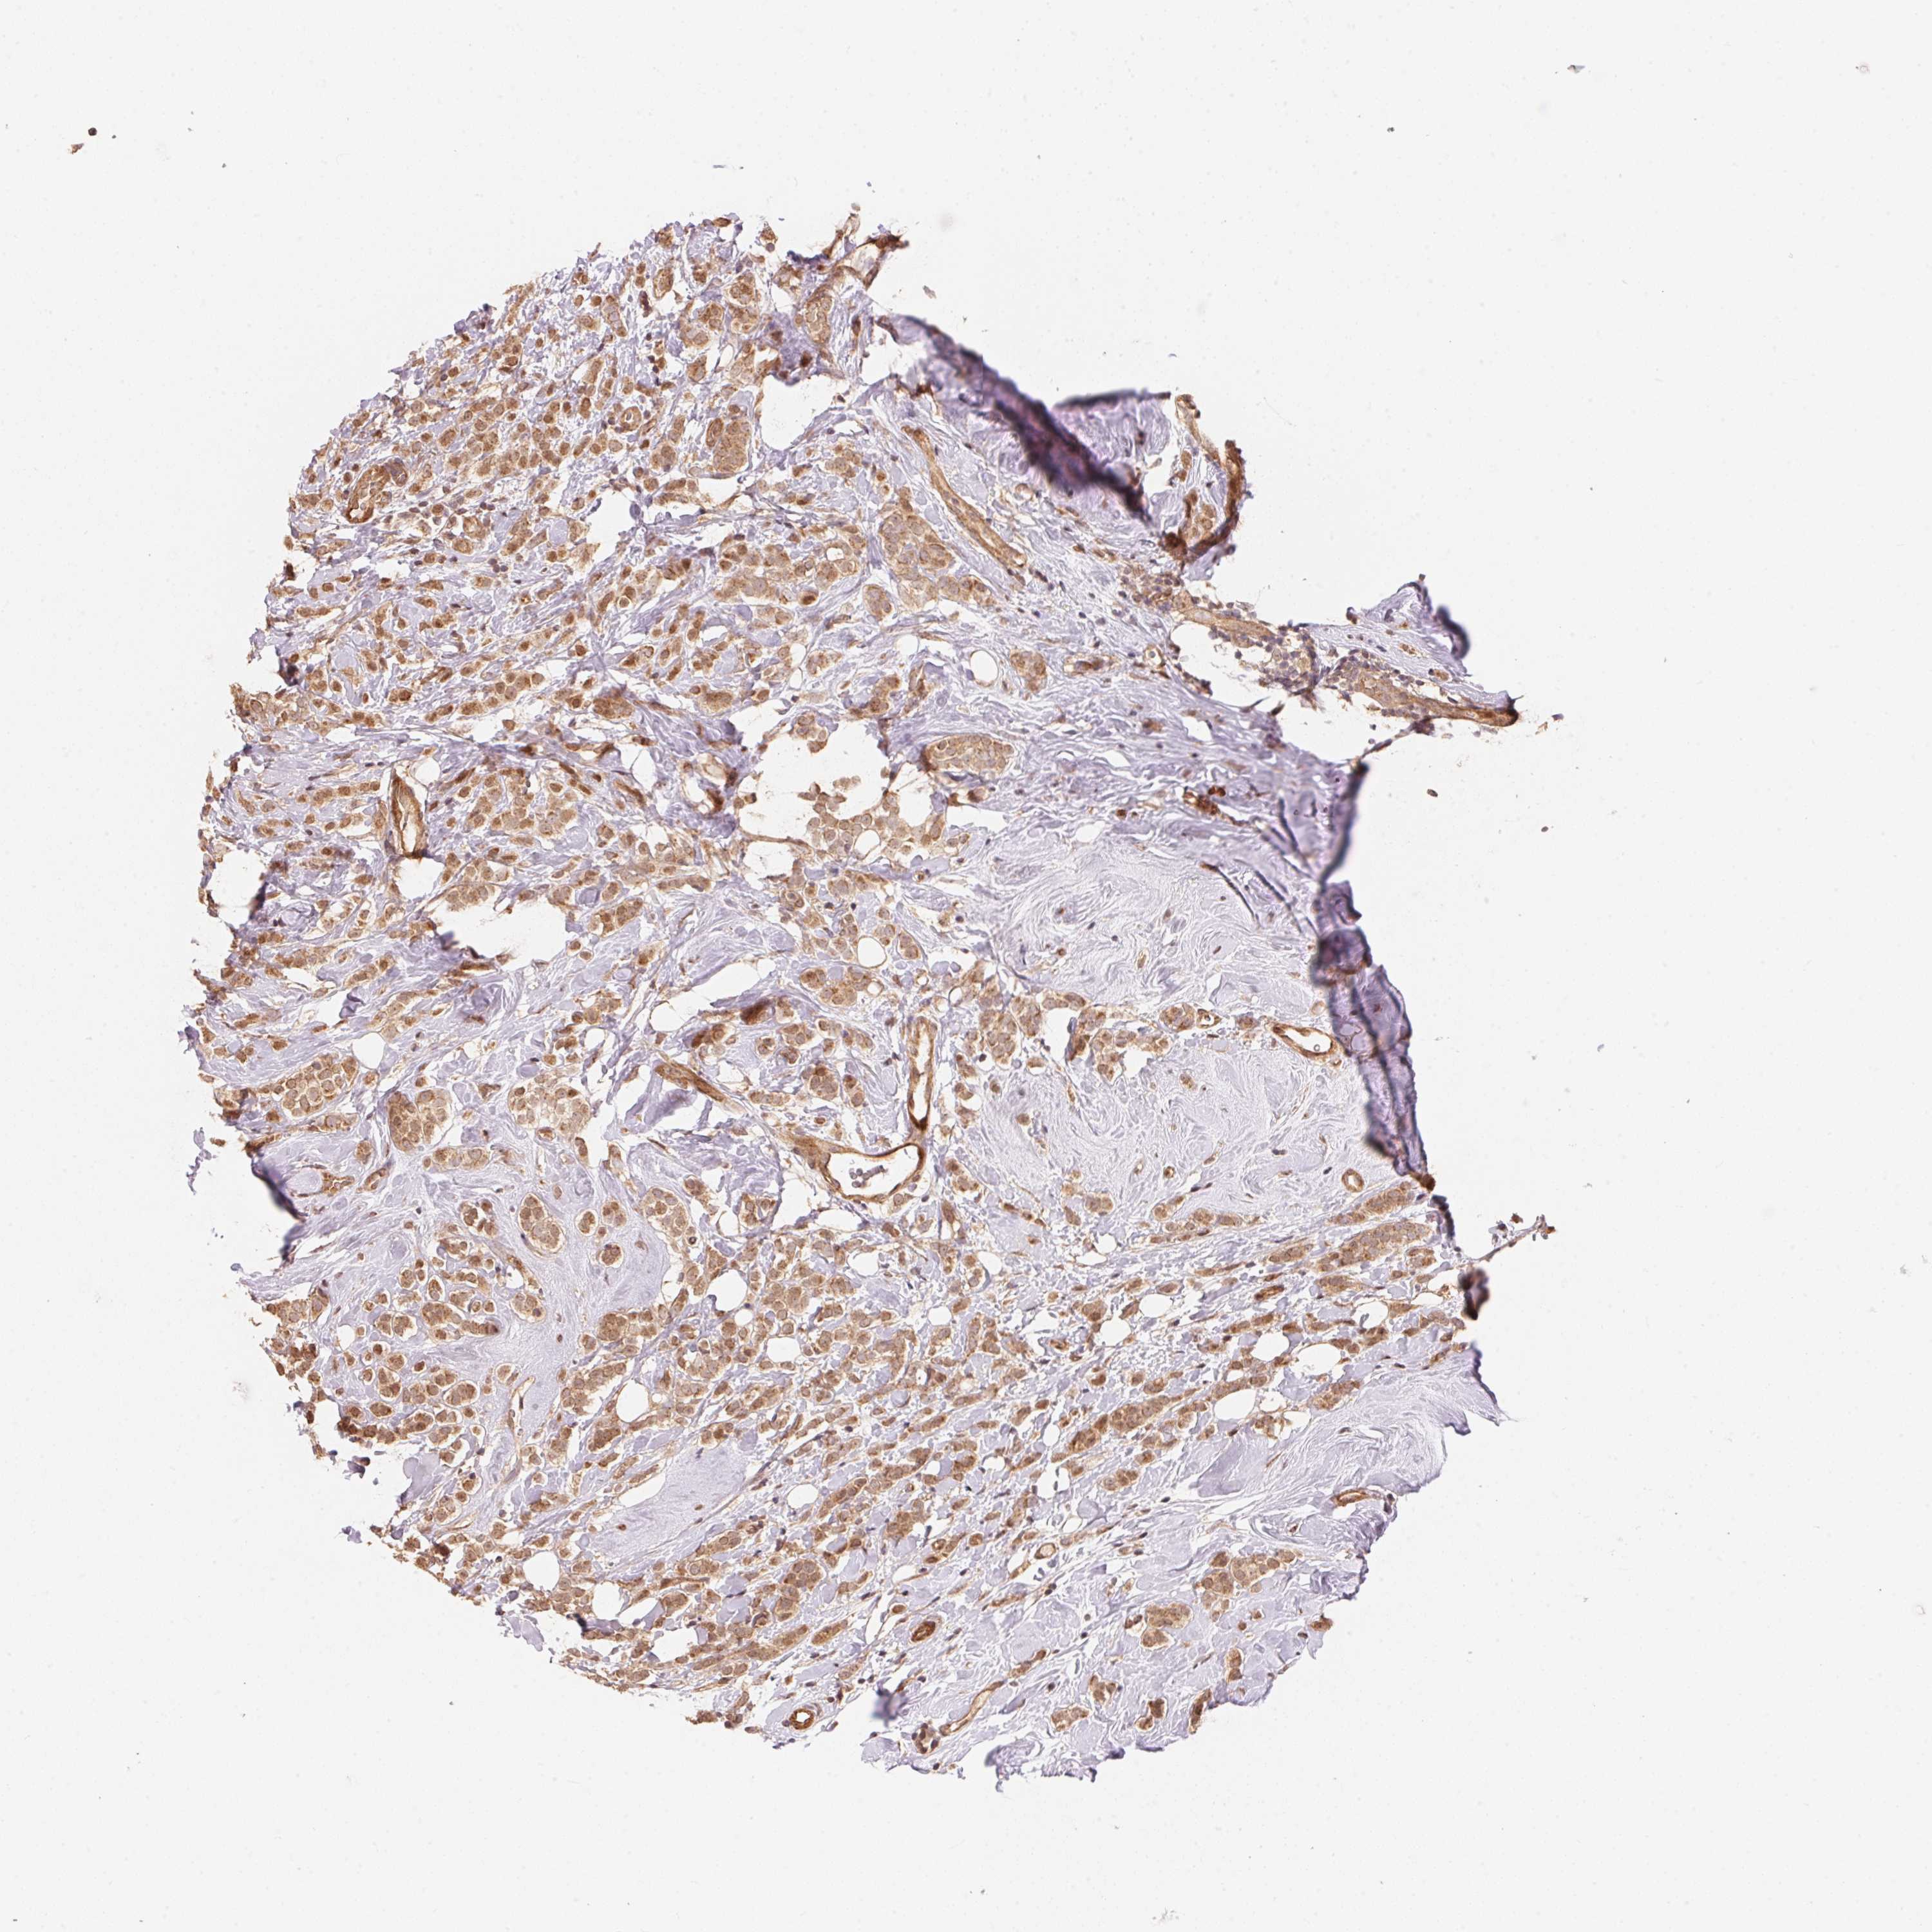

CANCER BREAST CANCER Show tissue menu

BRCA TCGA BRCA VALIDATION PROTEIN EXPRESSION

ANTIBODIES

AND

VALIDATION